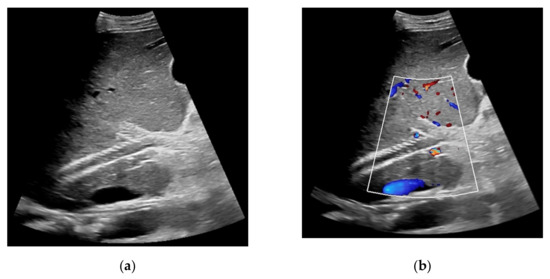

Figure 1. 65-year-old patient with regular visualization of the transjugular intrahepatic portosystemic shunt (TIPS) during B-mode (a) and adequate visualization of the TIPS in Color Doppler ultrasound (b) with inconspicuous flow and flow velocity (c).

Figure 2. 57-year-old female patient with occluded transjugular intrahepatic portosystemic shunt in B-mode (a) and consecutive absent flow signal in Color Doppler ultrasound (b).